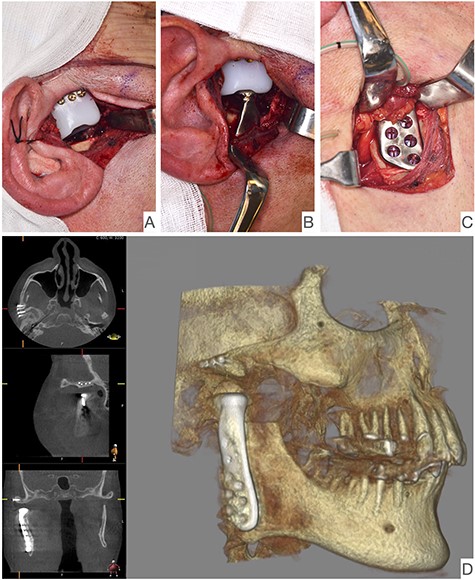

Shows postoperative CBCT after left TMJ replacement, 9 months after the right side.